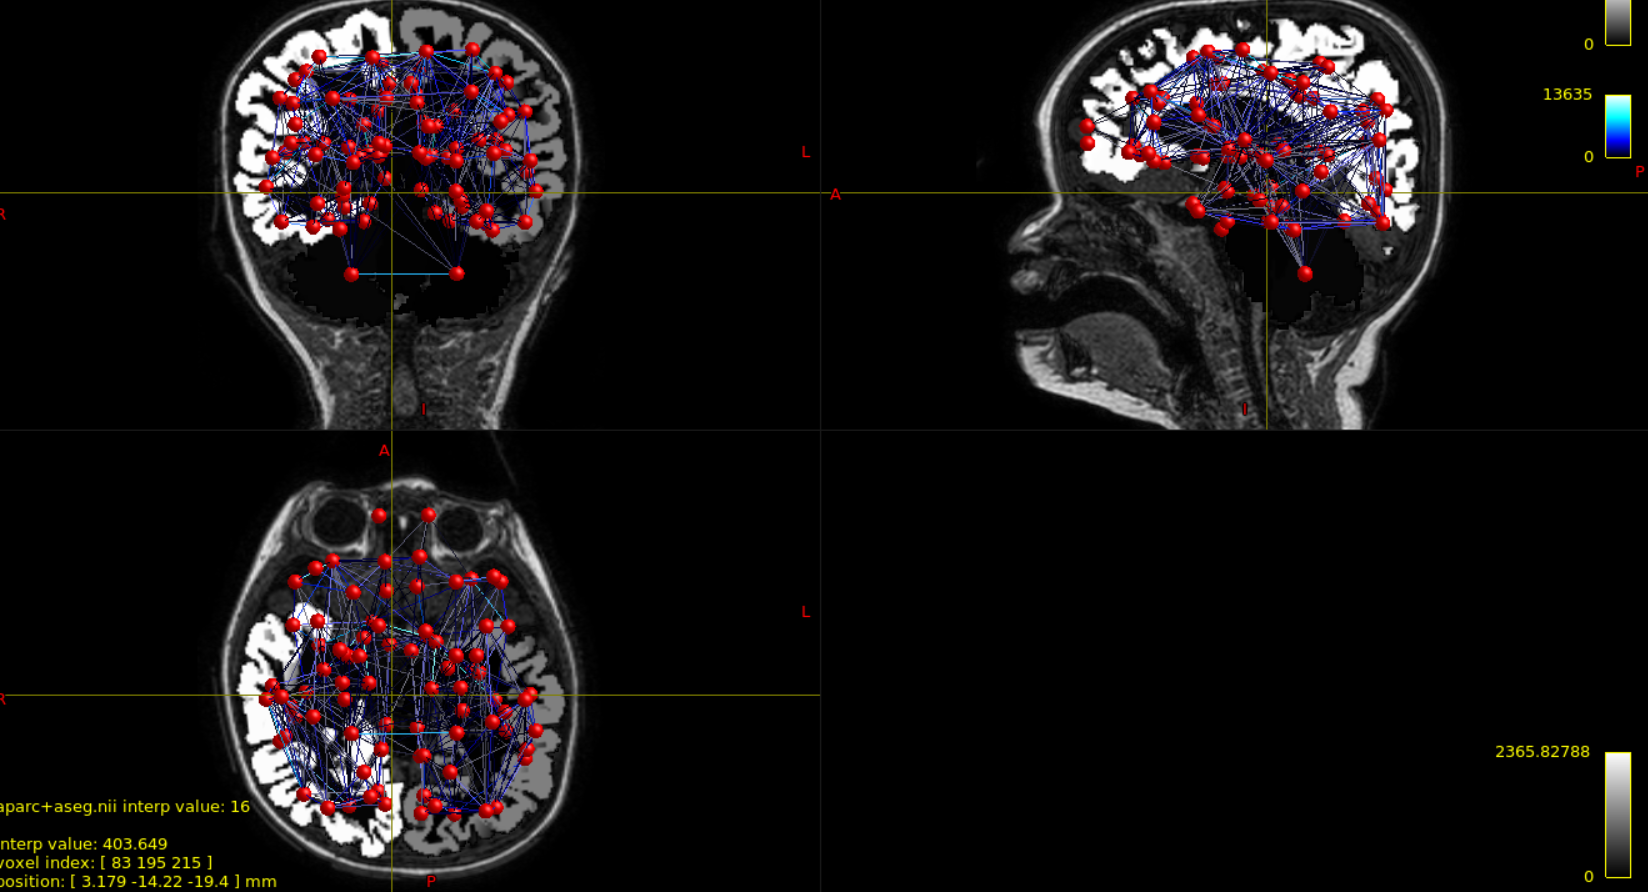

this is just to update you that I have tried visualizing the same example subject with Mrtrix3, and it seems input data are correct. As you can observe from the attached picture, aparc+aseg image excludes cerebellum and thus some nodes are outside it. The surface I use with BNV is created from this segmentation, so I think the outcome I obtain is expected.